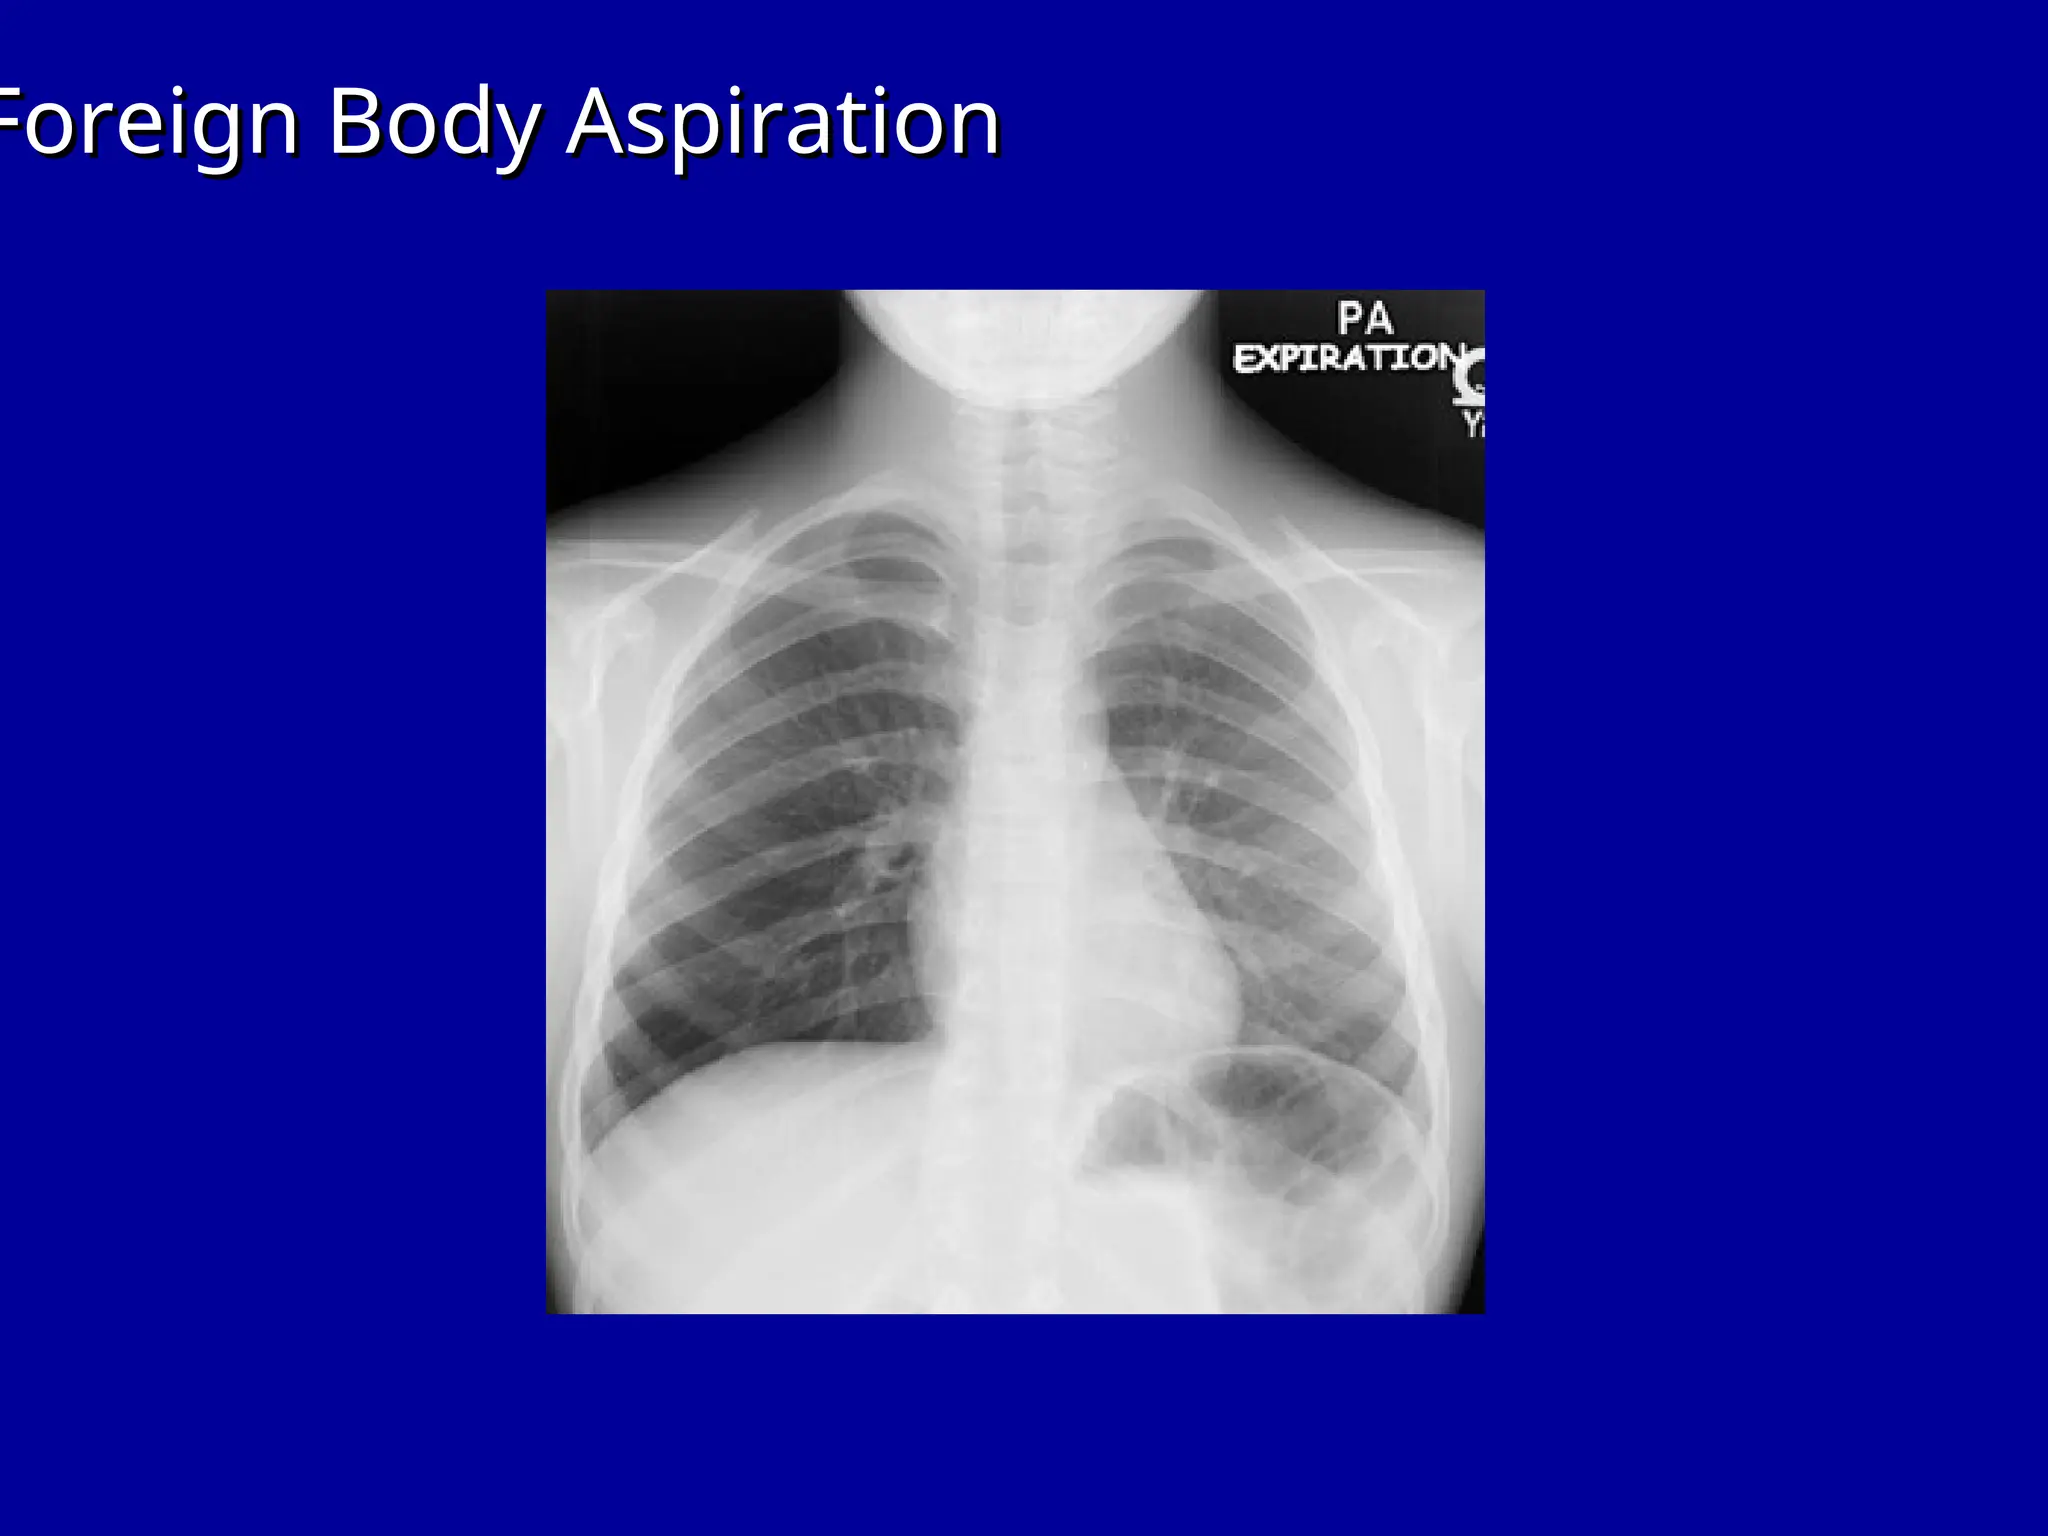

Foreign Body Aspiration

Right Lung

Atelectasis

Left Lung

Pneumonia